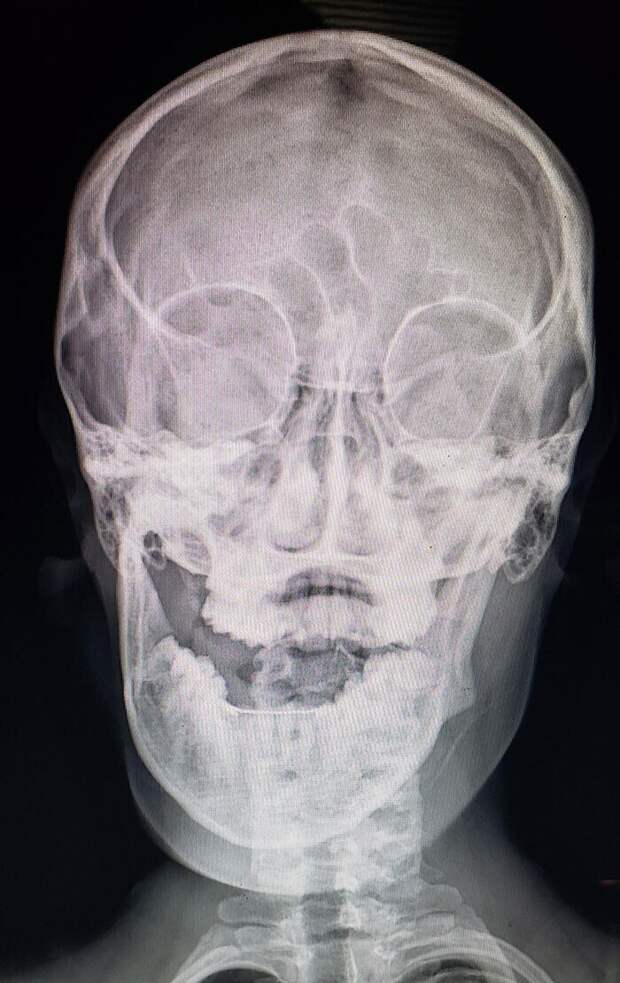

Ревматоидный артрит